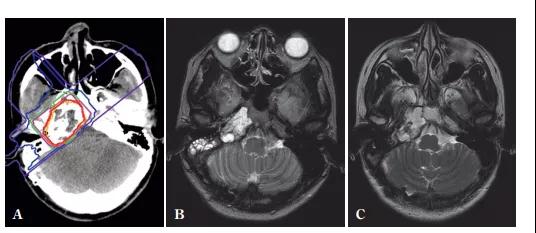

▲重離子治療骶骨脊索瘤,圖源:參考來源[3]

▲重離子治療骶骨脊索瘤,圖源:參考來源[4]